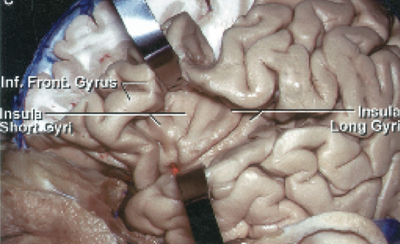

Insula cortex. BA 13-16 var ikke med i Brodmann's oprindelige klassifikation for mennesker men er homologe med de tilsvarende områder hos aber. Insulas cortex med lidt tilgrænsende anteriort temporalt beskrives samlet for BA 13-16